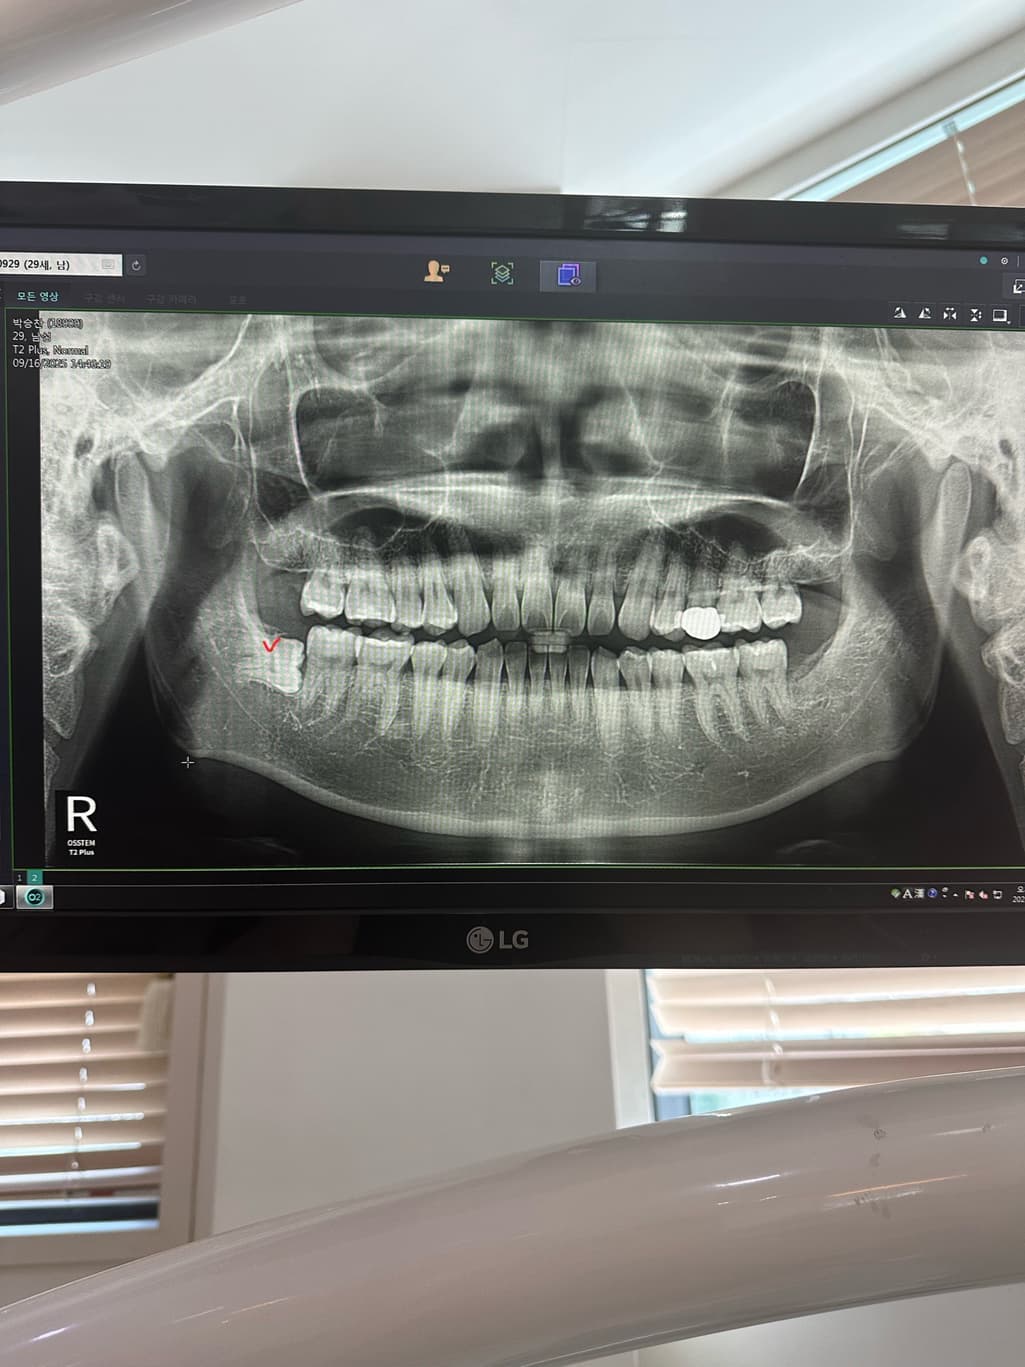

하악 매복사랑니 발치후 잇몸붓기 지속되는경우

완전옆으로 누여있는 사랑니 였고 이틀이후 얼굴에 멍이 올라올정도 였으며

• 2번 째 사진

사랑니의 매복된 정도를 봤을 때 뼈 삭제량도 많았을 것이라 붓기나 통증이 더 오래갈 것 같습니다.

사랑니 매복이 깊어서 잇몸 절개도 많이 햇고, 잇몸뼈 삭제를 많이 한경우에는 붓기가 몇일갈수도 있습니다.

매복사랑니 발치 과정에서 뼈도 다소 삭제하고 그랬다면 붓기는 일주일 이상 가기도 합니다.